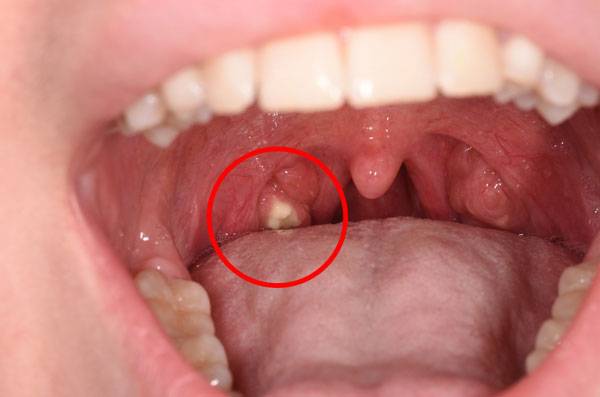

이를 닦아도 입냄새가 심하거나 음식을 먹지 않았는데도 목에 이물감이 느껴지면 편도결석을 의심할 수 있다.

편도결석은 편도선에 있는 구멍 사이에 낀 노란 알갱이를 말한다.

편도결석은 편도선에 있는 구멍 사이에 낀 노란 알갱이를 말한다. 음식물 찌꺼기에 세균이 번식해 부패되면서 만들어진 좁쌀만 한 크기의 덩어리이다. 강북보아스이비인후과의원 이철희 원장은 "편도선에는 원래 편도선와라고 하는 작은 구멍이 있는데, 음식물 찌꺼기가 입 안에 남아 있다가 이 구멍 안에 들어가면 뭉쳐서 편도결석이 된다"며 "주로 20~30대 성인에게 많이 생긴다"고 말했다.

구강상태가 청결하지 않거나 편도선염이 있는 사람에게 많이 생긴다. 이런 사람들은 구강 내에 세균이 증식할 가능성이 크기 때문이다. 편도결석은 치료를 받지 않아도 건강에 크게 문제되지 않는다. 알갱이가 어느 정도 커지거나 알갱이끼리 뭉치면 침을 뱉거나 양치질을 할 때 저절로 빠져나온다.

이철희 원장은 "편도결석이 생겼을 때 면봉 등으로 빼내면 환부에 염증이 생길 수 있으므로 저절로 나올 때까지 기다리거나 병원에서 소독한 의료 도구를 이용해 빼내야 한다"고 말했다. 편도결석은 빼내도 그 자리에 다시 생기는 경우가 적지 않은데, 재발이 반복되면 편도선절제술을 하는 경우도 있다. 예방을 위해서는 물을 자주 섭취하고, 양치질을 깨끗이 한 뒤 목 가글을 하면 좋다.